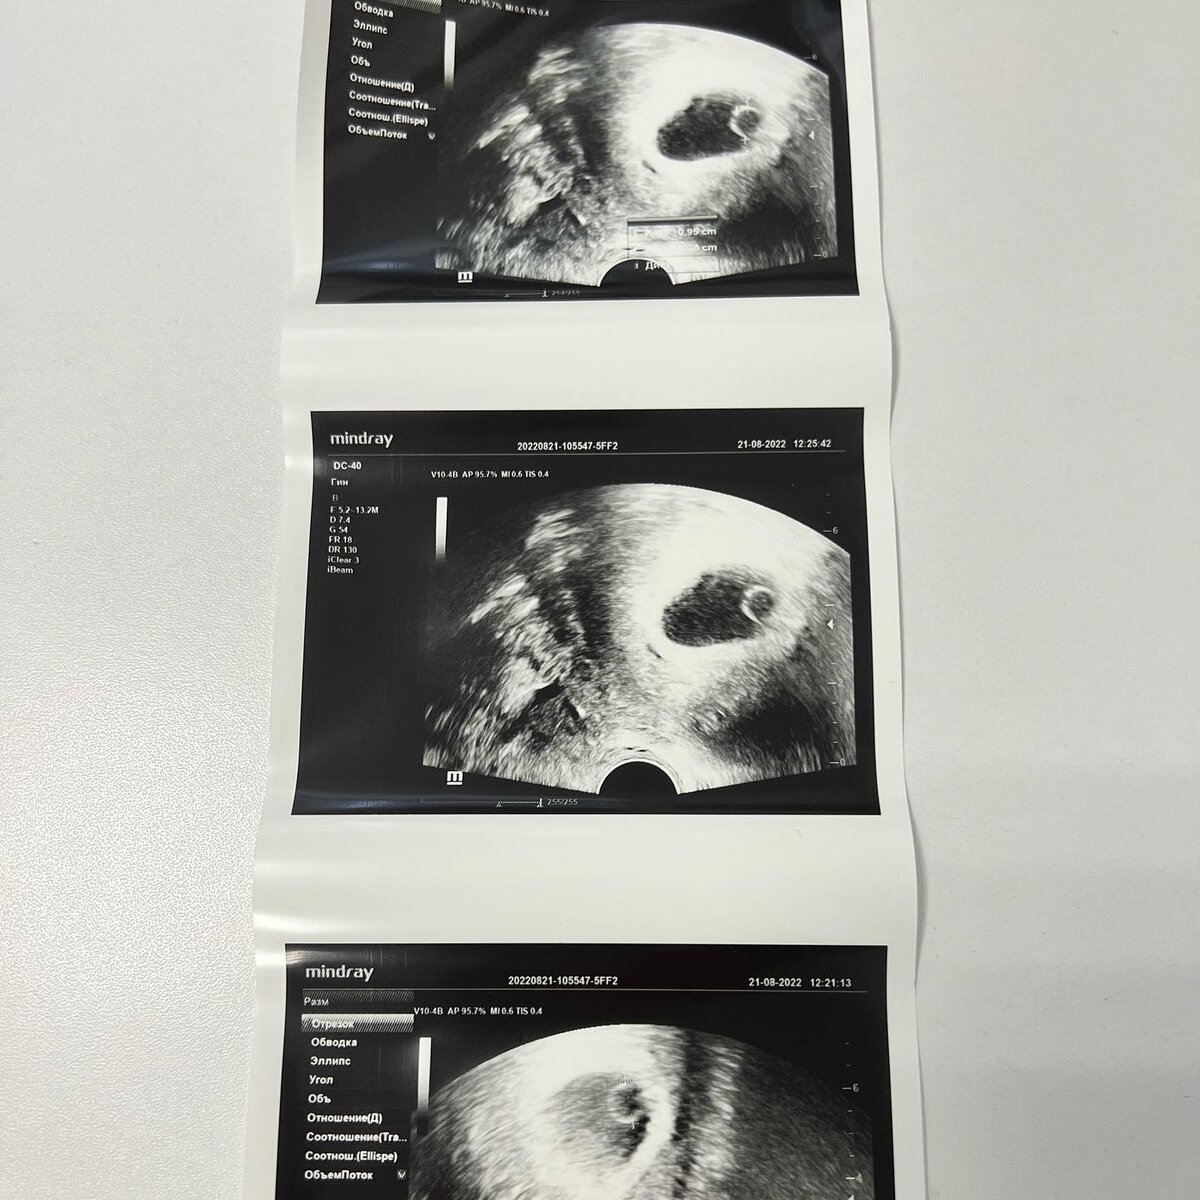

Есть беременность, 8 недель, есть плодное яйцо 3,4 см, а эмбриона внутри его нет.  Есть желточный мешочек. А эмбриона нет.  Это значит, что мне надо делать срочно делать аборт… Это называется анэмбриония. Я раньше не знала, что так бывает, но это случилось со мной.  Все подтвердилось вчера. Я пишу и плачу.  Это разновидность замершей беременности.  21 авг я сделала узи в платной клинике, в которой я наблюдалась. Там была картина такая же как вчера, но мы надеялись, что эмбрион «проявится». Я сделала два анализа ХГЧ, 21 и 25, - последний показал снижение на 10000, но мы все ещё надеялись. Вчера в ЖК мне сделали узи, где нужно было услышать сердцебиение, - два врача меня смотрели, - и там никого не было. Я сама видела, что там никого нет.   У меня болит грудь, матка увеличилась за неделю, мне малы мои шорты, но там никого нет(((  «От тебя тут ничего не зависело, если генетика эмбриона не сопоставима с жизнью, то развитие прекращается» - это мне пишет доктор в Вотсап, которая наб

21 авг я сделала узи в платной клинике, в которой я наблюдалась. Там была картина такая же как вчера, но мы надеялись, что эмбрион «проявится». Я сделала два анализа ХГЧ, 21 и 25, - последний показал снижение на 10000, но мы все ещё надеялись. Вчера в ЖК мне сделали узи, где нужно было услышать сердцебиение, - два врача меня смотрели, - и там никого не было. Я сама видела, что там никого нет.